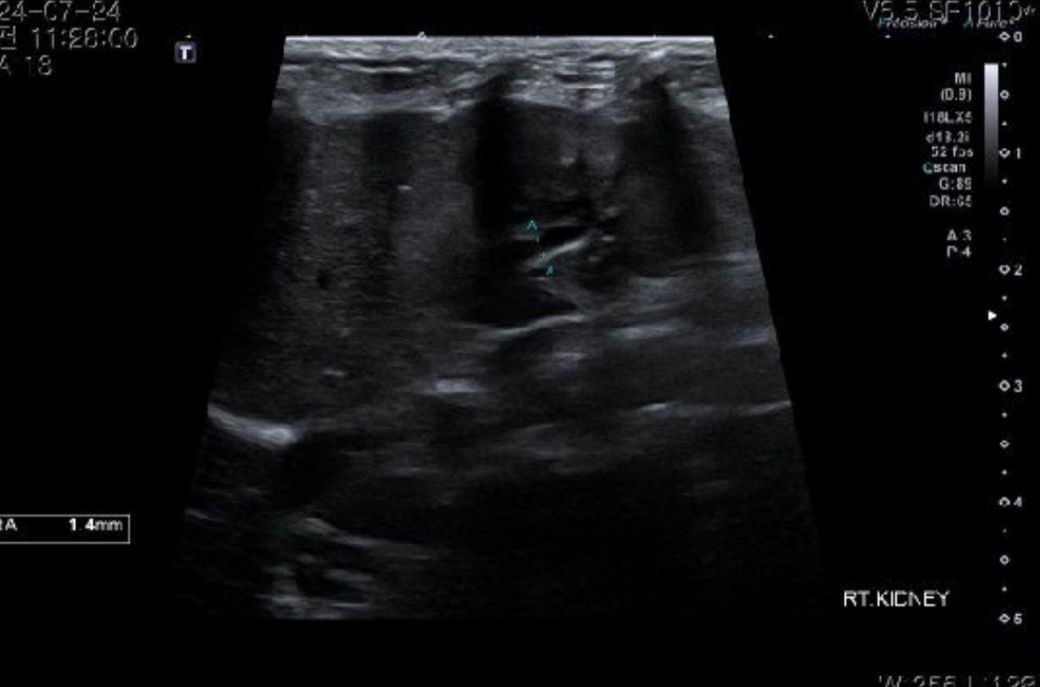

비장은 절제 수술 하기로 했습니다 .초음파상 혹들 어때보이나요ㅠㅠ?신장 물혹은 커서 수술할 때 물 빼도 무리는 안될까요????

초음파는 엑스레이나 CT, MRI 와는 다르게 검사를 한 검사자만이 판단을 할 수 있는 장비라 첨부된 사진은 별 의미가 없습니다. 시술자의 의견을 따르시기 바랍니다.